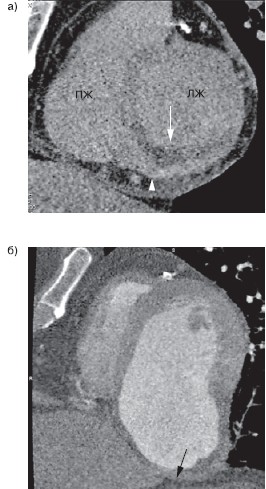

Рисунок 2. Томограммы сердца больного ОИМ нижней локализации (реконструкции изображений по короткой оси ЛЖ).

а — отсроченная МСКТ, выполненная на 3-и сутки ОИМ (стрелки — трансмуральный РДК миокарда базального сегмента нижней стенки ЛЖ, головка стрелки — субэпикардиальное отсроченное контрастирование); б — МСКТ, выполненная через 12 мес (стрелка — аневризма нижней стенки ЛЖ). ОИМ — острый инфаркт миокарда.

На томограммах, выполненных на 3-и сутки после ОИМ, определяется трансмуральный РДК миокарда нижней стенки ЛЖ с зоной субэпикардиального ОГК. Через 12 мес у этого больного сформировалась гигантская аневризма нижней стенки ЛЖ, больной был срочно госпитализирован в связи с острой СН.